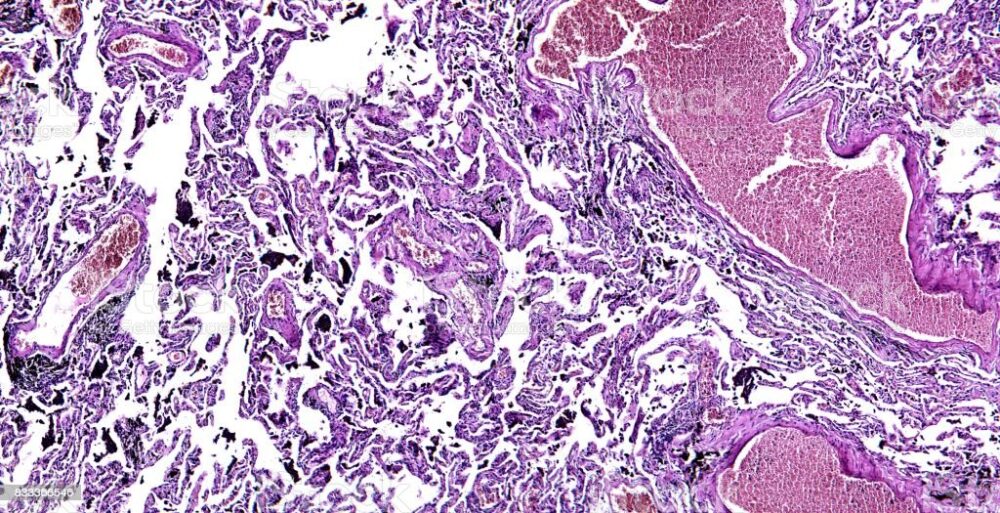

与单纯化疗组相比,联合治疗组的无事件生存率明显提高;癌症复发、进展或死亡的风险降低37%。而且,所有癌细胞完全消失,也就是完全缓解(CR)率,联合治疗组(24.0%),明显高于单纯化疗组(2.2%)。美国达纳-法伯癌症研究所的马克-阿瓦德(Mark Awad)是该临床试验的研究小组之一,他说:”完全缓解的患者也都接受了手术,对手术标本进行的病理检查结果显示:只有疤痕组织或纤维化组织,没有活的癌症组织,也没有发现活的癌细胞”。